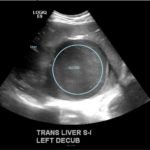

Although rare in the developed world, amebic infections are common worldwide and represent a challenging and often overlooked diagnosis. In this case, an amebic liver abscess was discovered in a 29-year-old male who presented to the emergency department (ED) complaining of right upper quadrant abdominal pain, weight loss, non-bilious/non-bloody vomiting, and diarrhea for three months. He recently traveled to India and Mexico. Point-of-care ultrasound discovered a liver mass and computed tomography (CT) confirmed the presence of a liver abscess. The case highlights the usefulness of ultrasound as an initial diagnostic tool, the importance of careful travel history in patients with suspected infectious diseases, and the initial provision of broad-spectrum coverage for bacterial and amebic pathogens for liver abscesses until the pathogen has been identified.